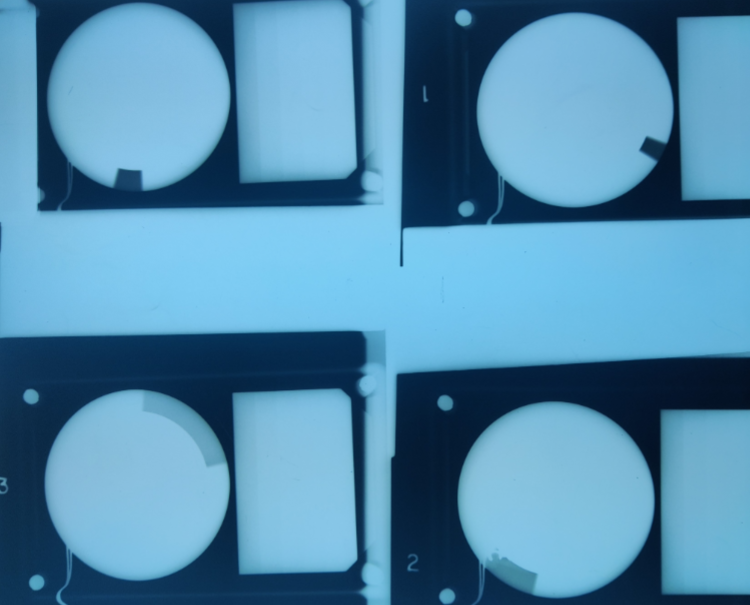

Q

Wisconsin kVp test. Used to test the accuracy of the kVp used during the exposure.